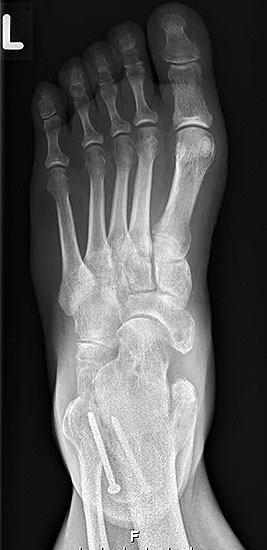

Stehende konventionelle Röntgenbilder eines Fußes mit Planovalgus Deformität Stadium II b dorsoplantar (dp) und seitlich. Auf der dp-Aufnahme zeigt sich die talo-calcaneare Divergenz, der gegenüber dem Kalkaneus nach anterior gleitende Talus und d

Abbildung 5

Stehende Aufnahmen des Fußes dorsoplantar (dp) und seitlich sowie des OSG anteroposterior (ap) sind die Grundlage der konventionellen Röntgendiagnostik (Abb. 5). Ergänzend werden gelegentlich die Rückfuβ-Alignement Aufnahme nach Saltzman 19 und Vergleichsaufnahmen der Gegenseite durchgeführt.

Der Talo-Metatarsale I Winkel bzw. die laterale talonaviculare Subluxation auf der stehenden dorsoplantaren Aufnahme des Fuβes dokumentieren das Ausmaβ des Vorfuβ abductus (Abb. 6 a,b). Ein dp Talo-Metatarsale I Winkel von > 10° (nach medial konvex) ist als pathologisch anzusehen. Mit der Bestimmung der talocalcanearen Divergenz (Abb. 6 c) erhält man ein Eindruck über das Ausmaβ des Rückfuβ valgus; eine leichte Divergenz bis ca. 12° gilt als physiologisch 20.

Auf der seitlichen, stehenden Aufnahme des Fußes wird ebenfalls der laterale Talo-Metatarsale I Winkel (Abb. 6 d) gemessen und so das kollabierte mediale Längsgewölbe dokumentiert. Auch hier gilt ein Talo-Metatarsale I Winkel von > 5° (nach plantar konvex) als pathologisch 21. Der Kollaps findet dabei meist im Talonaviculargelenk, seltener in der Naviculocuneiform-Gelenkreihe statt. Instabilität und Arthrose im 1. TMT sollten ausgeschlossen oder bei der Operationsplanung mit einbezogen werden. Weitere wichtige radiologische Messungen zur Beurteilung der Planovalgus-Statik und Progression der Deformität sind der laterale talo-calcaneare Winkel (Abb. 6 e) und der Abstand des Os cuneiforme-Unterrandes zum Untergrund (Abb. 6 f, Cuneiform height, 22. Eine anteriore Translation des Talus auf dem Kalkaneus findet man sowohl auf der ap, als auch auf der seitlichen Aufnahme des Fuβes mit Aufhebung der Cima-Linie.

Die stehende OSG ap -Aufnahme kann zunächst das fibulocalcaneare Impingement und im Endstadium laterale OSG Arthrose oder Valgus-Tilt des Talus zeigen.